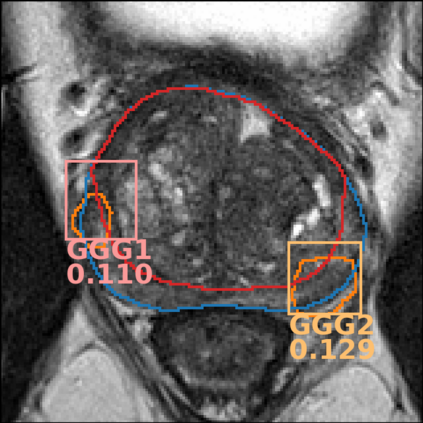

The emergence of multi-parametric magnetic resonance imaging (mpMRI) has had a profound impact on the diagnosis of prostate cancers (PCa), which is the most prevalent malignancy in males in the western world, enabling a better selection of patients for confirmation biopsy. However, analyzing these images is complex even for experts, hence opening an opportunity for computer-aided diagnosis systems to seize. This paper proposes a fully automatic system based on Deep Learning that takes a prostate mpMRI from a PCa-suspect patient and, by leveraging the Retina U-Net detection framework, locates PCa lesions, segments them, and predicts their most likely Gleason grade group (GGG). It uses 490 mpMRIs for training/validation, and 75 patients for testing from two different datasets: ProstateX and IVO (Valencia Oncology Institute Foundation). In the test set, it achieves an excellent lesion-level AUC/sensitivity/specificity for the GGG$\geq$2 significance criterion of 0.96/1.00/0.79 for the ProstateX dataset, and 0.95/1.00/0.80 for the IVO dataset. Evaluated at a patient level, the results are 0.87/1.00/0.375 in ProstateX, and 0.91/1.00/0.762 in IVO. Furthermore, on the online ProstateX grand challenge, the model obtained an AUC of 0.85 (0.87 when trained only on the ProstateX data, tying up with the original winner of the challenge). For expert comparison, IVO radiologist's PI-RADS 4 sensitivity/specificity were 0.88/0.56 at a lesion level, and 0.85/0.58 at a patient level. Additional subsystems for automatic prostate zonal segmentation and mpMRI non-rigid sequence registration were also employed to produce the final fully automated system. The code for the ProstateX-trained system has been made openly available at https://github.com/OscarPellicer/prostate_lesion_detection. We hope that this will represent a landmark for future research to use, compare and improve upon.